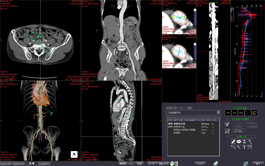

The PET/CT Fusion protocol provides flexible and simple image overlay analysis. Standard Uptake Value calculations are enabled with ROIs and VOIs.

MULTI-MODALITY FUSION

Up to four different series from different phases or even modalities can be layered using varied opacity profiles.

The Multi-Data Fusion protocol highlights spatial relationships between objects that can assist in planning surgical procedures.